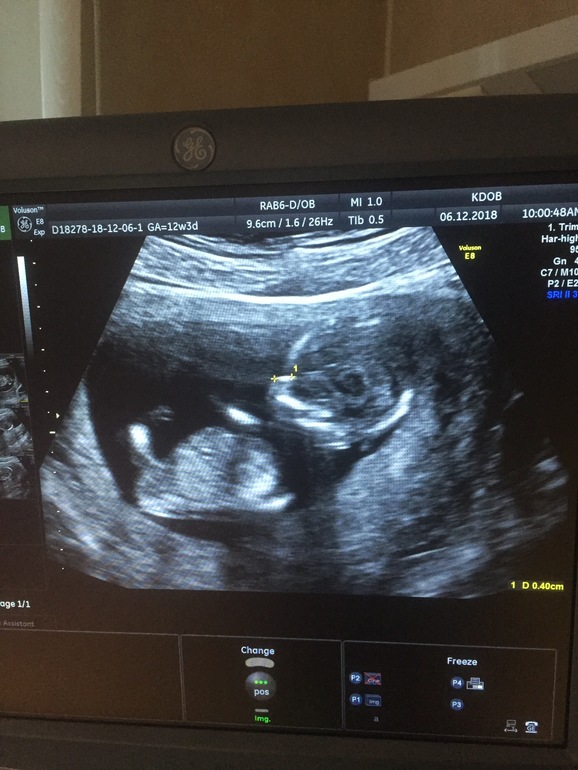

1 скрининг ))))

Образ жизни до, во время и после ЭКОДобрый вечер, девочки! ))) Ну вот и прошёл наш 1-ый скрининг,это непередаваемые эмоции.

Какое счастье видеть своего пупсика , муж смотрел не отрываясь от монитора ! 🥰🥰🥰Малышик то на спинку, то на бочок , то ручку в рот )))), даже помахал нам 🙈🥰😁.Расти и крепчай наше солнышко.Ктр 6,8 у нас )))) , срок по узи ставят больше 13 неделек и 1 .😊Пол нам не сказали , но для меня это неважно , лишь бы мое счастье было здоровым и крепеньким! Кровушка будет готова на следующей неделе, но я знаю что у нас все хорошо.

22 января все узнаем , если конечно пупсик нам покажется .